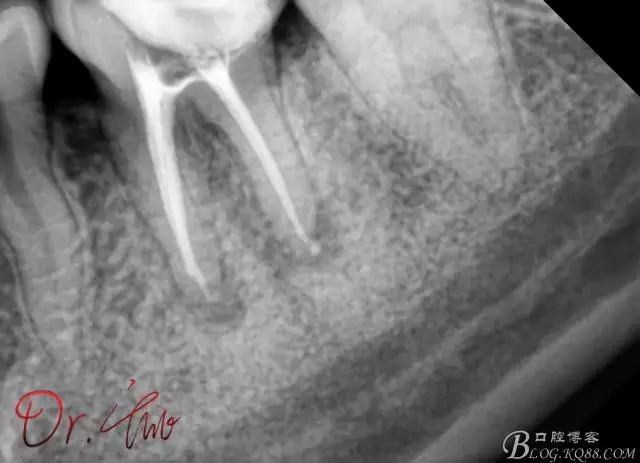

第一次試主尖

640.webp (2).jpg

第二次試主尖

640.webp (3).jpg